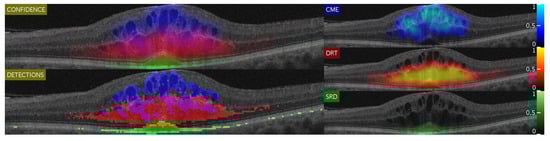

An example of the results that can be generated by this strategy is represented in Figure 6. As can be seen in this image, despite the binary map showing a set of false positives, the confidence maps actually highlight the correct regions as important. The same way, specially in the case of DRT, it is interesting to also analyze any detection, as even expert clinicians have issues detecting where or where not the diffuse limits of the DRT end.

Figure 6.

Example of a generated image showing all five different points of view. As shown, leftmost representations give a general idea of the interaction between DME types. On the other hand, the rightmost maps present a more detailed characterization.

By doing so, we can obtain a matrix composed by three feature vectors (one for each type of DME and optimal features defined by the SFS algorithm for each class). These classifications are used by two different complementary algorithms, the Confidence map and the Binary map. Finally, when the two types of maps are generated, its information is used to generate an intuitive visualization of the detection and characterization of the different ME types to facilitate their inspection by the specialists. This visualization consists in a 5-window representation of different points of view of the detections with two main representations:

- The “CONFIDENCE” window shows a merged representation of all the pathology confidences and the interactions between them. This window allows experts to study the possible overlap between the types of pathology that cannot be achieved through segmentation. In addition, it clearly presents the interactions that cannot be observed in the windows of the other types on their own. With this same idea (displaying the confidence on the detections), the 3 right-sided windows show, independently, each of the confidences given by the confidence map algorithm, but using a color map with a higher degree of granularity (so an expert clinician can see the nuances between in the confidence levels).

- The “DETECTIONS” window represents all the detections, without displaying the confidence the system infers in them. This allows the experts to have a different perspective of the detections, showing a more explicit representation of the independent regions that have tested as positive (as well as an interpolation of the surrounding regions that may also be candidates). In doing so, it complements the information shown in the “CONFIDENCE” window.